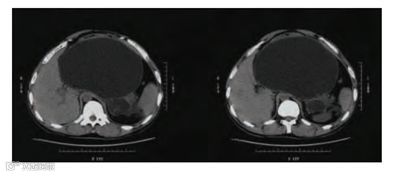

腹部CT提示胰腺巨大假性囊肿压迫胃部